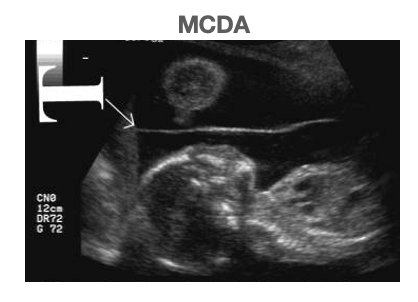

13

Q

What US sign is associated with monochorionic diamniotic twins?

A

T sign

• there is a membrane between the twins

• the T represents separation of the amniotic sacs

How well did you know this?